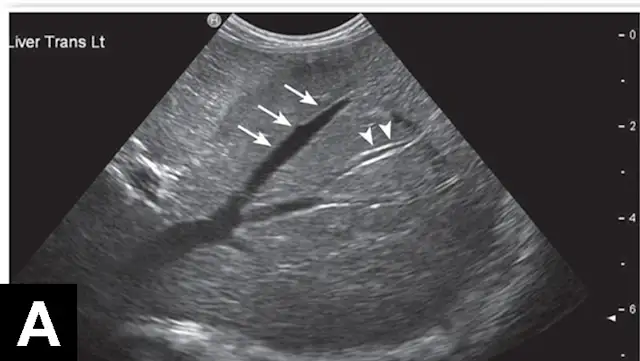

Figure 1A

In each of these cases, histologic diagnosis was made using fine-needle aspirates of the liver (vacuolar hepatopathy, hepatic lipidosis, acute severe neutrophilic hepatitis, respectively). Transverse image (A) of the left side of the liver in a normal dog showing hepatic vein (arrows) and portal vein (arrowheads). Hyperechoic liver (B) secondary to glycogen accumulation resulting from Cushing’s disease in a dog. Note the decrease in portal vascular markings. Hyperechoic and hyperattenuating liver (C) secondary to hepatic lipidosis in a cat. Note the hypoechoic falciform fat in the near field (≤1.5 cm deep) relative to liver echogenicity. In addition, there are some contact artifacts resulting in hyperechoic lines as well as the normal lines of abdominal musculature in the extreme near field (<0.5 cm). In normal cats, falciform fat and hepatic echogenicity are isoechoic to each other. In the far field, hyperattenuation of the ultrasound beam results in image dropout (starting at a depth of 3.5 cm). Hypoechoic liver (D) secondary to acute hepatitis in a dog. Note the marked decrease in echogenicity relative to the spleen.